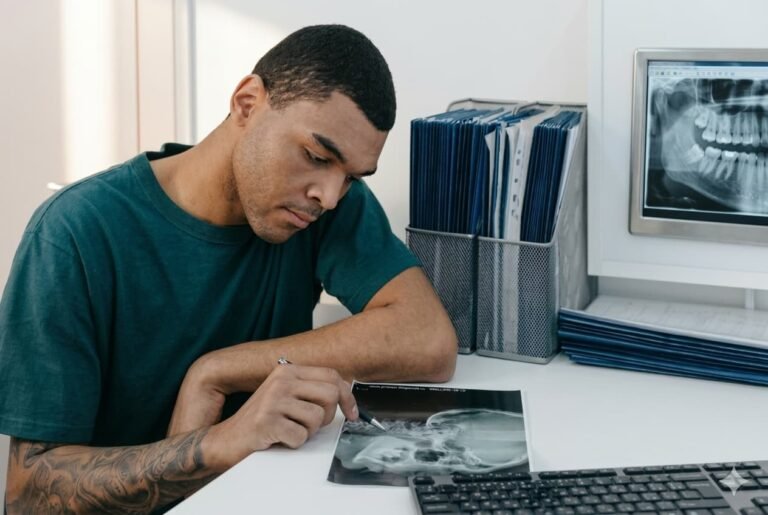

Tecnología en Odontología: Transformando la Experiencia del Paciente

15 diciembre, 2025 | by focrisaralda.com

La Inteligencia Artificial (IA) en Odontología

15 febrero, 2025 | by focrisaralda.com

¿Qué puede hacer la inteligencia artificial en odontología? La Inteligencia...